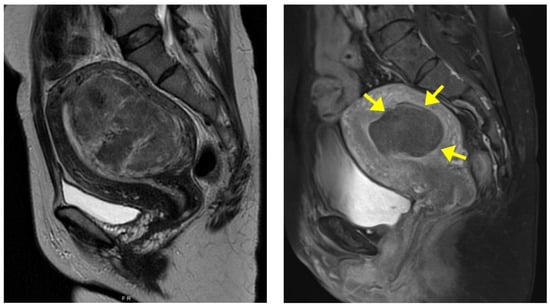

Of the 75 fibroid cases, 28 (37.3%) were Type 2 fibroids according to the International Federation of Gynaecology and Obstetrics (FIGO) classification [], 17 (22.7%) were Types 2–5, 13 (17.3%) were Types 3–4, 13 (17.3%) were Type 5, and 4 (5.4%) were Type 6. The baseline fibroid volume median was 190.1 cm3 (range: 18.5–1729.4 cm3). Table 2 summarizes the fibroid volumes at 6 and 12 months after treatment and their corresponding percentage volume reduction. The images of one of the patients before and 6 months after HIFU are shown in Figure 2. The symptom severity scores (SSS) using the modified UFS-QOL questionnaire median before treatment was 28 (range: 19–35). The scores at 6 and 12 months after treatment are summarized in Table 2.

Figure 2.

Magnetic resonance (MR) images of a fibroid from a 40-year-old woman; (Left) pre-HIFU MR image showing a large anterior uterine fibroid; (Right) Post-HIFU MR image, 6 months after treatment, showing a hypoperfused well-defined area (arrows) as the result of HIFU with a 73.9% reduction in fibroid volume.